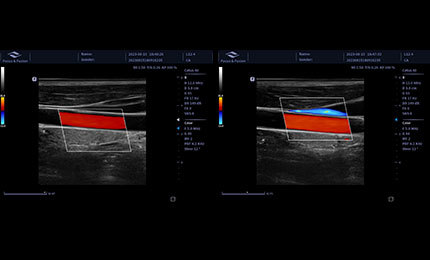

Automatyczna identyfikacja i pomiar grubości błony wewnętrznej i środkowej. Możliwość pomiaru zarówno lewego, jak i prawego naczynia krwionośnego, ściany przedniej i tylnej.

Szybkie ponowne lokalizowanie obszaru zainteresowania (ROI) na naczyniu krwionośnym za pomocą jednego przycisku. Zmniejsza obciążenie lekarza związanego z częstym dostosowywaniem pozycji i kąta ROI w zależności od różnych lokalizacji naczynia, poprawiając efektywność pracy.